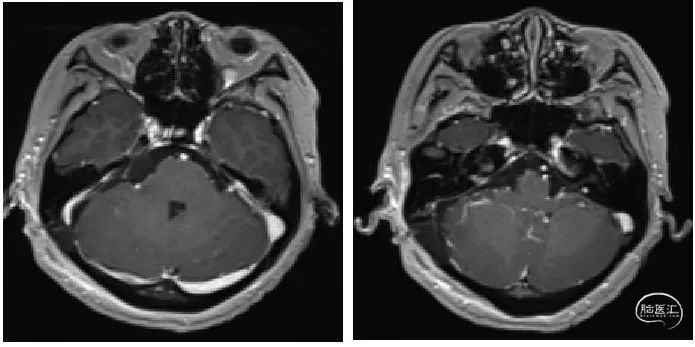

术前T1增强序列示:肿瘤位于桥小脑角处,不均匀强化伴囊性变。

术后影像